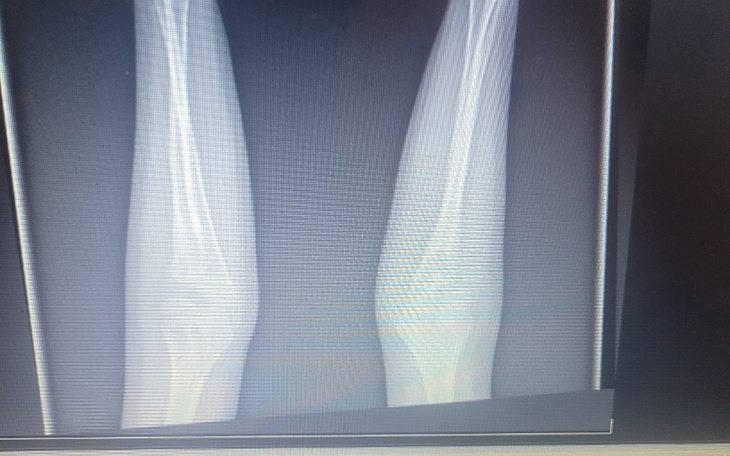

Witam jestem samotną matką wychowujacą 2 dzieci jestem doknieta przemocą domową! Najstarszy syn ma 9 lat a najmłodszy syn ma 20 miesiecy, u starszego syna wykryto wadę wrodzoną w postaci Kościozrostu promieniowo-łokciowy obustronne, w obu stawach w lewej jak i w prawej strony. Syn jest praworęczny, i właśnie w prawym łokciu ma największą wadę gdyż każdy rengent ktory syn przechodzi w przychodni ortopedycznej sprawia mu ból i prowadzi go do płaczu... Po kilku konsultacjach u różnych specjalistów zaden nie chce podjac sie operacji ze względu na łamanie mu kości i wprowadzeniu mu implantów stawowo-łokciowych. Gdyż jakis lekarz podejmie sie operacji będzie czekała nas rehabilitacja i powrót do funkcjonowania rąk, i podstawowych czynnosciach takich jak, pisanie, wiązanie butów, czy zapięcia ekspresów czy nawet zapieciu guzików, na rehabilitacje długo się czeka, dlatego utworzyłam zbiórkę żeby synowi pomóc odnaleźć się w podstawowych czynnosciach w rehabilitowaniu tych rąk oraz sprzetu do rehabilitacji. Za kazdą pomoc dziekuje

Jesteśmy po wizycie u ortopedy czekamy na termin operacji pod narkozą